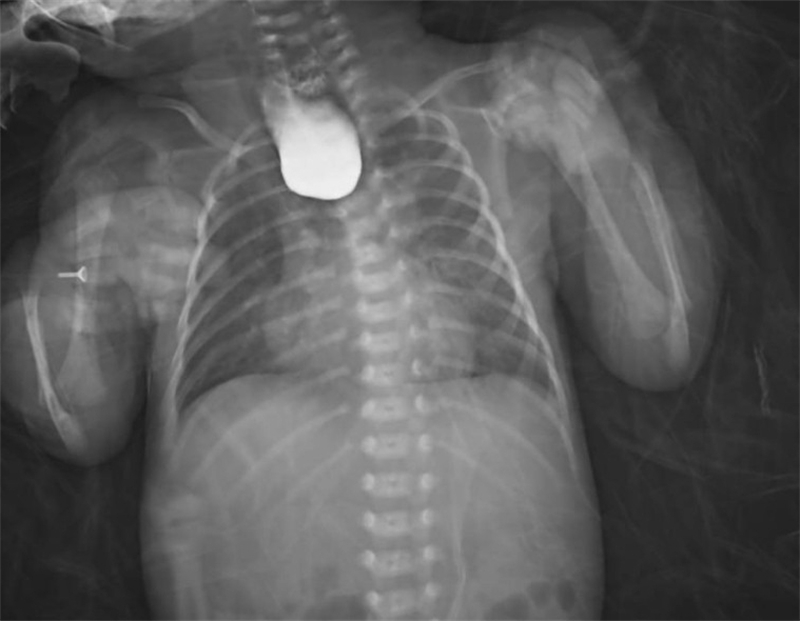

面對這一突發(fā)情況,經(jīng)驗豐富的新生兒科醫(yī)生立即警覺:萱萱有可能患有少見且嚴重的新生兒先天性疾病——食管閉鎖。為了盡快明確診斷,新生兒科與小兒外科討論后,緊急聯(lián)系放射科為萱萱安排了消化道造影、CT掃描等全面檢查。最終,檢查結(jié)果明確診斷:先天性食管閉鎖Ⅲ型伴食管氣管瘺。

術(shù)后僅1天,萱萱便能通過留置胃管接受腸內(nèi)營養(yǎng)支持。在新生兒科醫(yī)護人員的精心照料下,術(shù)后3周復(fù)查消化道造影顯示手術(shù)切口愈合良好,萱萱終于可以自己吃奶啦!